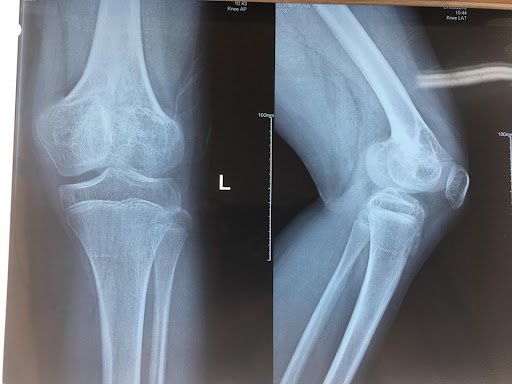

- Các sụn tăng trưởng xung quanh đầu gối thường nhạy cảm hơn ở các khu vực khác. Gãy sụn tăng trưởng ở đầu gối có thể gây biến dạng chi khiến chân ngắn hơn, dài hơn hoặc cong vẹo nếu sụn tăng trưởng bị tổn thương vĩnh viễn. Tổn thương sụn tăng trưởng ở những vùng xung quanh cổ tay và vai thường nhanh lành hơn mà không có vấn đề gì.